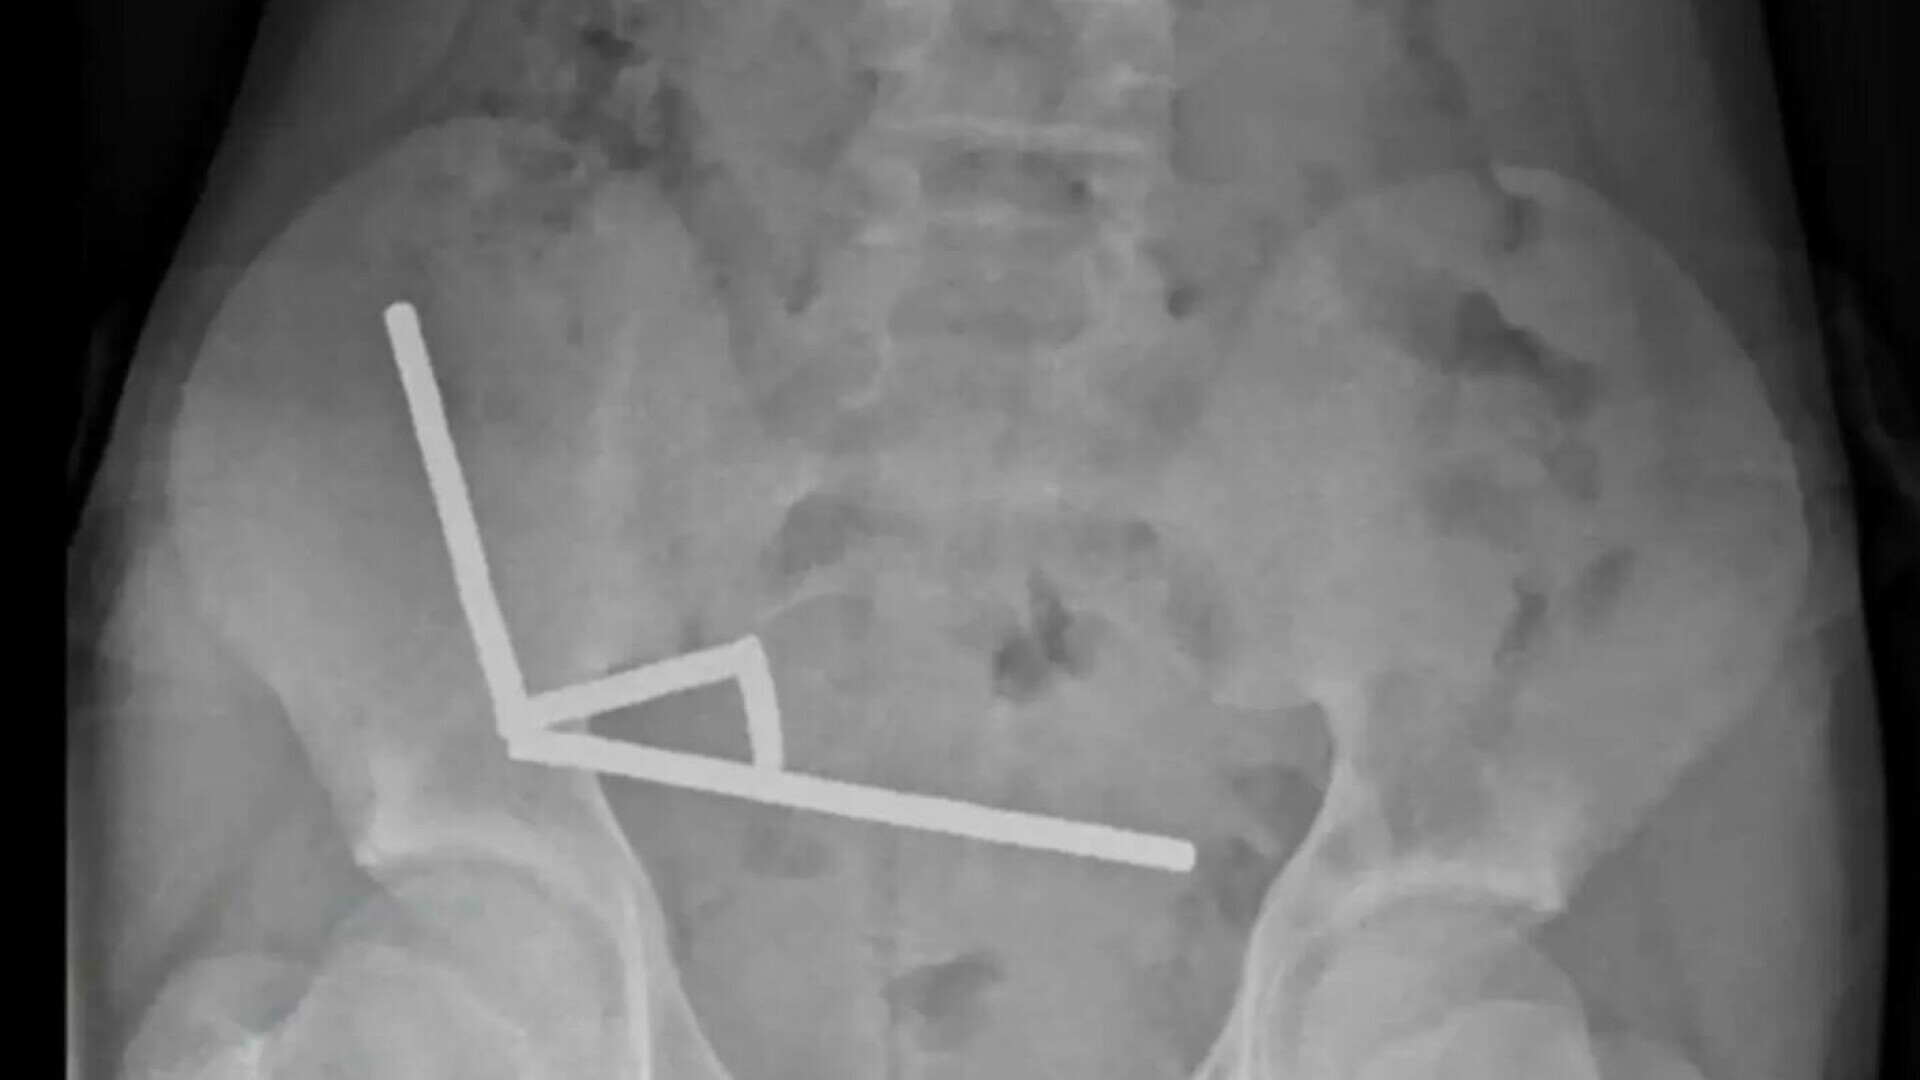

Radiografiile au arătat patru lanțuri de magneți blocate în diferite secțiuni ale intestinelor, care se atrăgeau reciproc și blocau fluxul sanguin către țesutul din apropiere. Medicii au explicat că această presiune a provocat multiple zone de necroză – adică zone de mucoasă intestinală moartă – ceea ce a necesitat o operație de urgență.